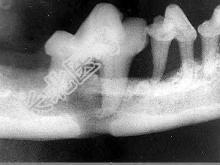

- 单项选择题颌面外伤患者,咬合错乱, 下唇麻木张口受限,经X 线检查如图。应该为 ( )

D、下颌骨骨折